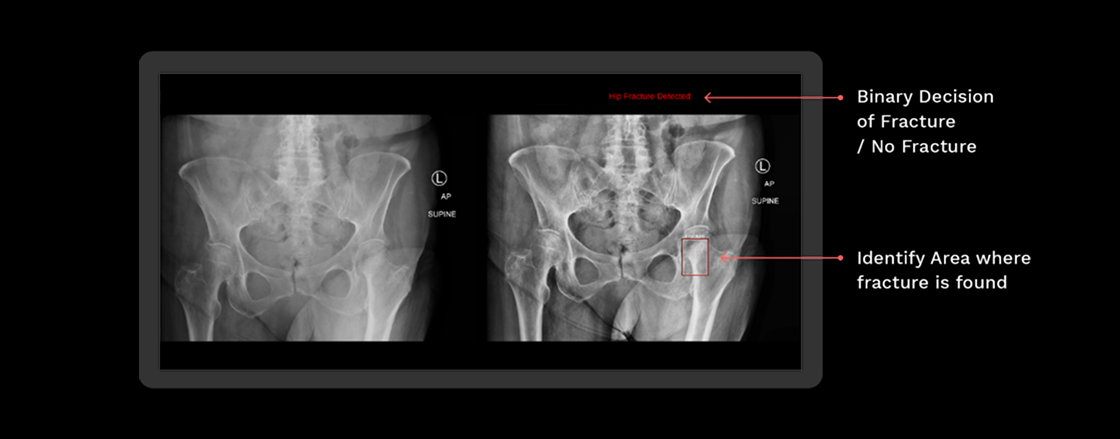

Rbfracture™

AI-powered, automatic detection of trauma-related findings

Benefits of using RBfracture™

Supports trauma

reads 24/7

Improved diagnostic

accuracy

Suggested diagnosis

within seconds

Clinical Trial

Trial showing improved diagnostic accuracy for Emergency Care residents when

reviewing hip fracture X-rays

Above shows the change using RBfracture™ has had on reviewing hip fracture images by reader group